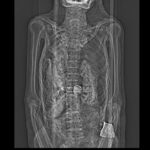

In 1996, cross-sectional images of the entire mummy were taken using computed tomography (CT). A scout view (left) illustrates the approximate position and size of the scarab. On a CT scan (right), it is clearly visible as a bright, i.e. very dense object between linen bandages and ribs.